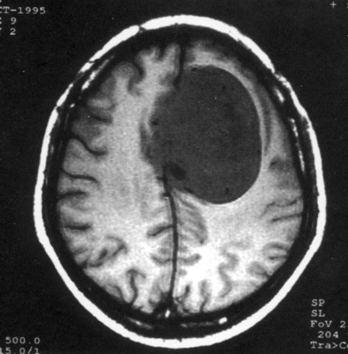

问题 病历摘要:??患者,男,40岁。发作性左下肢抽搐1年余,每次发作3~5分,每周发作1~2次。每次发作后感左下肢乏力,约半日后可自行恢复。既往身体健康。体检:神清,头顶部偏右有局限性骨性隆起(1.5×1.5cm),左鼻唇沟稍浅,伸舌居中。感觉、运动无明显异常。左浅反射减退,左下肢腱反射稍亢进,左Babinski征(-)。 下列对该患者的临床特点分析哪些是正确的?

选项 A.有Jackson癫痫发作 B.有Todd氏麻痹 C.有精神运动性癫痫发作 D.右中央前回可能有刺激性病灶存在 E.右中央后回可能有破坏性病灶存在 F.有失张力发作 G.右锥体束征(+) H.有颅内高压表现

答案 ABDG

解析 ABDG